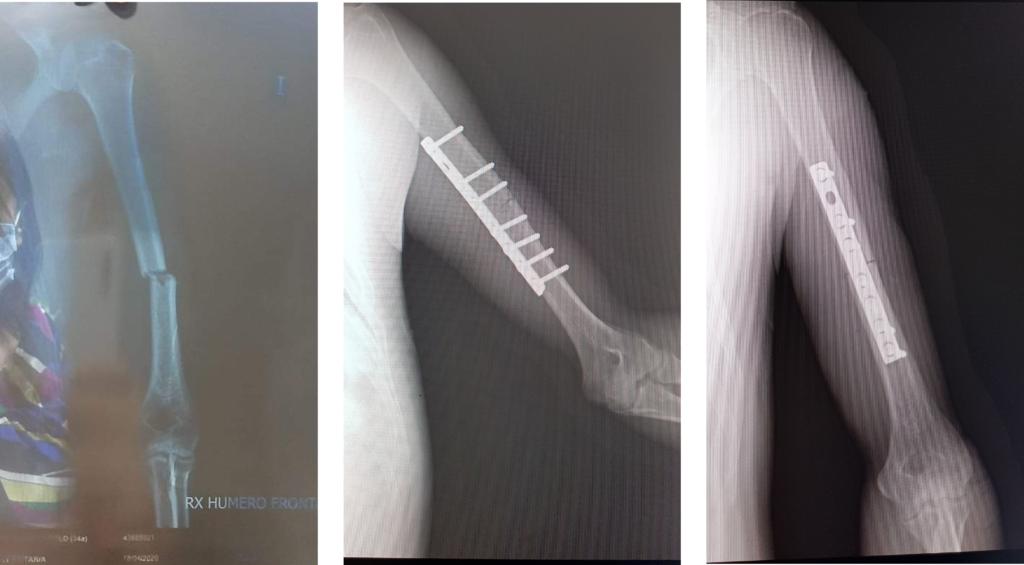

Paciente varón de 34 años de edad con antecedente de caída en vía pública. Cae al resbalar sobre piso mojado mientras usa sandalias. Dx fractura de húmero diafisiario izquierdo el día 18/04 operado el 07/05 del mismo año.